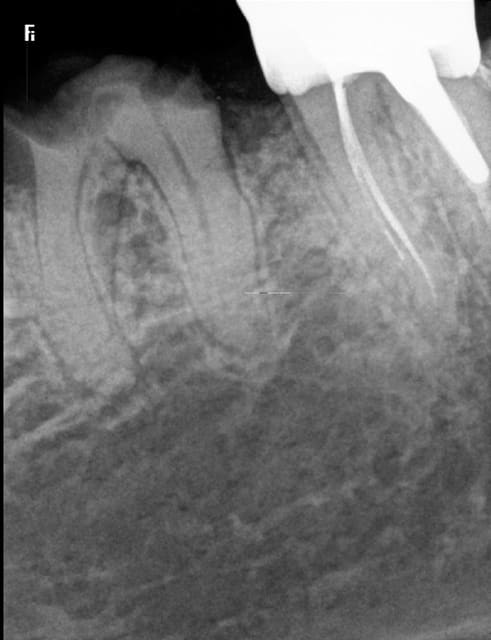

Moi je fais. Mais j ai des aides optiques..je vais retrouver une radio d un traitement de correspondant que j ai fait il y a peu tu me diras si c est ressemblant

traitement fait juste avec loupes. l'ouverture de la chambre et trouver les entrées canalaires ca a été coton mais faisable..1h30 de traitement tout de même

Mme durif annette 1 azvr6d - Eugenol

Mme durif annette 4 kdtmtm - Eugenol

manquait celle ci désolé

Mme durif annette 2 makpln - Eugenol